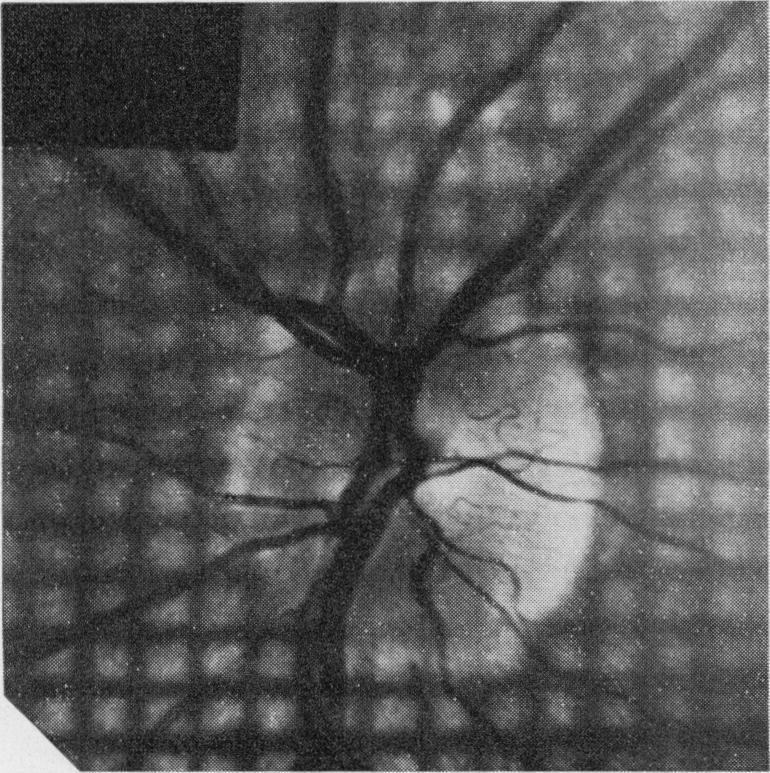

Shadows on the disc.

Proc R Soc Med. 1971 Sep;64(9):938-9. doi: 10.1177/003591577106400927.

https://cdn.ncbi.nlm.nih.gov/pmc/blobs/ea83/1812867/ffd1f9319806/procrsmed00278-0091-b.jpg

https://cdn.ncbi.nlm.nih.gov/pmc/blobs/ea83/1812867/94ded058d061/procrsmed00278-0091-a.jpg